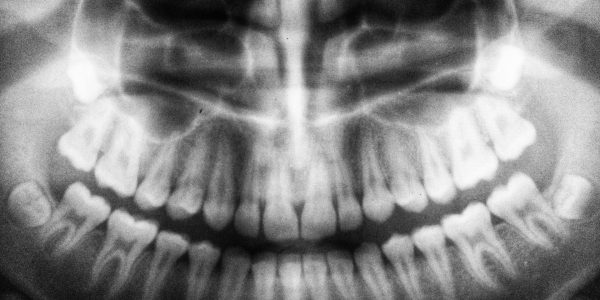

Postępowanie stomatologiczne z ósemkami

Ósemki, zwane potocznie zębami mądrości, zwykle wyrastają między 17. a 30. rokiem życia, ale nie u wszystkich dorosłych. Niestety, kiedy już się pojawią, „lubią” sprawiać problemy. Dlaczego? Przeczytaj poniżej, dlaczego usuwa się ósemki i czy ekstrakcja ósemek jest bolesna. Dlaczego…

Leczenie choroby okluzyjnej

Wiele osób zastanawia się, jakie są przyczyny choroby okluzyjnej. Ponadto ludzie nie wiedzą, jakie są możliwości leczenia takiej choroby. Warto zaznaczyć, że okluzja w stomatologii oznacza relację między zębami górnymi a dolnymi. Zaburzenie prawidłowego zwarcia zębów objawia się nieestetycznym uśmiechem,…